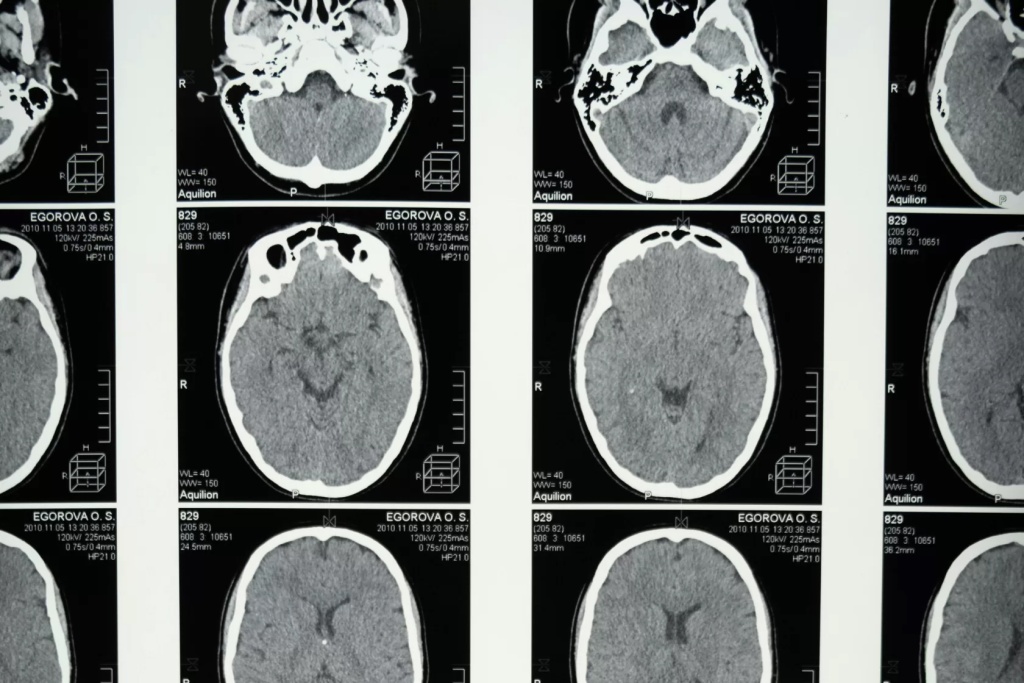

МРТ (магнитно-резонансная томография) – это метод исследования, основанный на использовании магнитного поля и радиоволн. Режимы МРТ – это различные способы обработки сигнала, полученного во время исследования.

1 МРТ 2.jpg

Первые МРТ-сканеры были разработаны в 1970-х годах. Изначально они давали только черно-белые изображения с низким разрешением. Со временем технологии МРТ развивались, и сегодня мы можем получать цветные изображения с высоким разрешением, которые позволяют увидеть мельчайшие детали анатомии.

Исторически режимы МРТ начали появляться сразу после изобретения самого метода в начале 1970-х годов. С развитием технологий и исследований по физике магнитного резонанса были разработаны новые методики и алгоритмы для улучшения качества и информативности получаемых изображений. Это включало в себя разработку различных последовательностей импульсов, таких как T1-взвешенные, T2-взвешенные, протонно-плотностные, а также различные методы усиления контраста, такие как гадолиниевые контрастные средства.